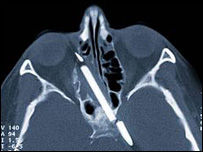

中國日報網環球在線消息:數十年來,德國女子瑪格麗特·韋格納時常感到頭痛,並經常流鼻血,但是醫生卻對她的這一症狀有些無可奈何。

原因是沒人敢在她的大腦裡做手術,取出藏身於那裡50多年的一截鉛筆。據德國《圖片報》8月6日報導,韋格納4歲的時候出了一次意外,她不慎摔倒,手裡握著的一根鉛筆剛好插進她的大腦裡。

所幸鉛筆與大腦內部的重要部位“擦肩而過”,這才使得韋格納得以安然成長至今。可腦中異物的存在卻令她時常感到頭痛還伴有流鼻血的症狀。數十年來,韋格納一直希望能取出腦中的那個“禍根”,但是受到技術限制,沒有任何醫生敢冒風險給她做這一手術。

如今,韋格納已經59歲,醫學手段的發展令韋格納終於可以擺脫鉛筆給她帶來的惡夢。德國一家醫院最近為韋格納做了腦部手術,取出了鉛筆的大部分(大約8厘米)。但是,仍有大約2厘米的殘餘因為已經與部分腦部組織牢固地長在了一起,只能繼續留在顱中。

鉛筆穿過韋格納的鼻孔插入頭顱

格納4歲的時候出了一次意外,她不慎摔倒,手裡握著的一根鉛筆剛好插進她的大腦裡。